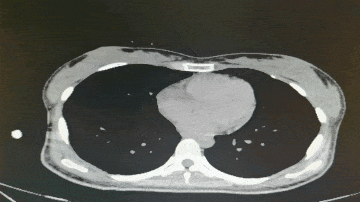

2023年3月2日 腹部CT

◈ 2023年3月2日,患者来院复查腹部CT提示:中腹部小肠局部见缝合线影,吻合口未见异常强化影,盆腔内见液体密度影。腹腔脂肪间隙稍浑浊,网膜稍增厚。腹壁见瘢痕影。左下腹前腹膜区见小结节影,大小约0.6cm×0.8cm,轻度强化。

◈ 检查诊断:1、符合部分小肠术后,吻合口未见异常强化影。2、盆腔积液,对比前片积液量减少。3、腹腔脂肪间隙稍浑浊,网膜稍增厚,较前片减轻。4、左下腹前腹膜区小结节。